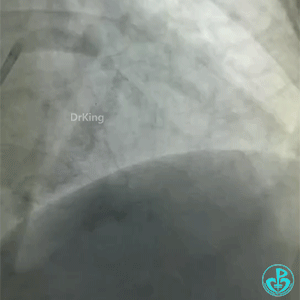

导丝怎么扩真怪!急性心梗前降支导丝通过顺利,球囊扩张后导丝移位很多!不在原来的血管腔!_https://www.jmylbn.com_新闻资讯_第3张

再进一根导丝,可以在对角支和主支随意进出,随后病人血流变慢,症状有加重,后面的造影血流更慢。